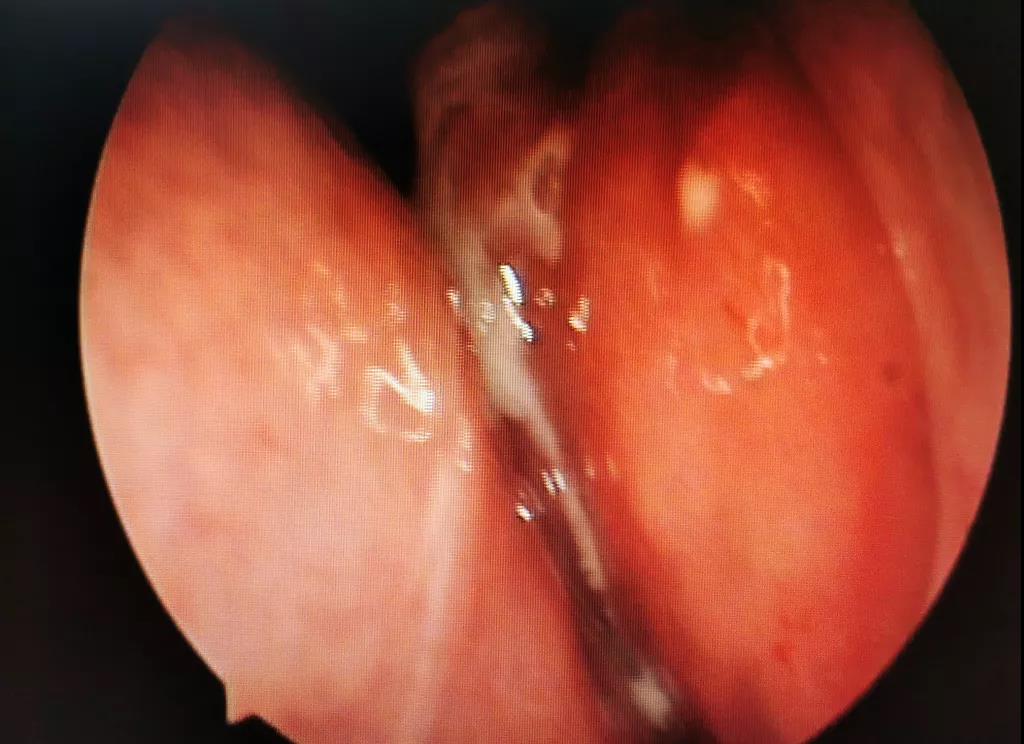

(魏大叔鼻內(nèi)鏡圖示)

通過鼻內(nèi)鏡檢查發(fā)現(xiàn),魏大叔左鼻道有半透明息肉樣新生物,表面附著黃色膿性物。再結(jié)合魏大叔的癥狀及CT報告,黃博士高度懷疑魏大叔是真菌性鼻竇炎,建議魏大叔行手術(shù)治療。